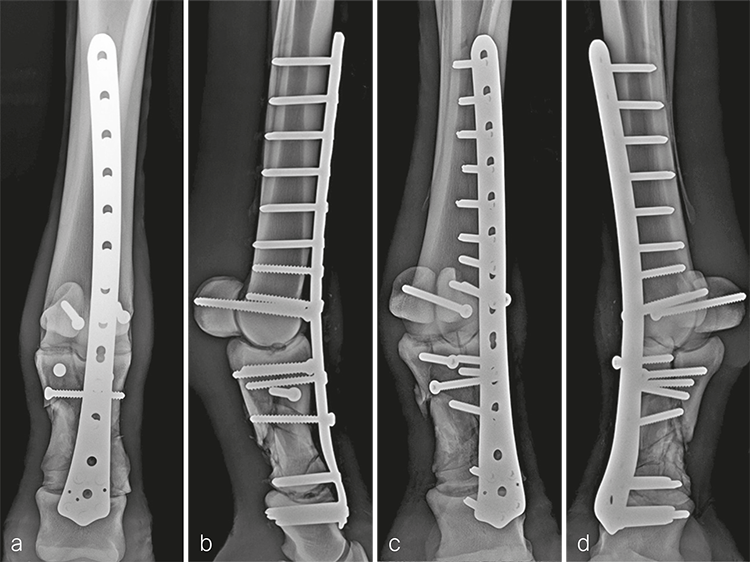

Following recovery from anesthesia, the mare was placed in intensive care for 24 hours to stabilize her physiological status before surgical fixation. Bridging plate fixation of the comminuted P1 fracture in conjunction with arthrodesis of the metacarpophalangeal and proximal interphalangeal joints was accomplished using an LCP DFP (11-holes). Prior to fixation, articular cartilage was debrided from the articulations using a 4.5 mm drill bit and curettes passed through stab incisions. The frontal plane fracture in the proximal aspect of P1 was reduced and stabilized with 5.5 mm cortex screws placed in lag fashion from dorsal to palmar in a slightly distal to proximal orientation.

The plate was contoured to the desired 15 of dorsiflexion at the level of the fetlock joint to provide an appropriate joint angle (Fig 4a). Three, approximately 4 cm long dorsal midline incisions were performed through the skin and extensor tendon at the level of the proximal end of the plate, the metacarpophalangeal joint, and at the distal end of the plate overlying the proximal interphalangeal joint. Using a combination of sharp dissection and a large periosteal elevator, a tunnel was created between the bone and overlying soft tissues including the extensor tendon. The plate was inserted into the tunnel and appropriate plate positioning, and cortical alignment were confirmed radiographically. A Push-Pull Reduction Device was placed through hole (A) in the head of the plate at the level of the proximal interphalangeal joint to compress the plate onto the dorsal cortices of the phalanges and maintain alignment of the proximal interphalangeal joint. Five 5.0 mm locking screws were inserted in the expanded head of the plate to purchase the distal aspect of P1 and the proximal aspect of P2. To ensure plate-bone contact proximally, two 5.5 mm cortex screws were placed into the distal aspect of the metacarpus (plate shaft holes 4 and 5). The remaining holes overlying the metacarpus were filled with 5.0 mm locking screws; where possible, 4.5 mm cortex screws were placed through the plate overlying large fragments of the P1. Finally, two 5.5 mm cortex screws were placed in lag fashion abaxial to the plate to engage the medial and lateral proximal sesamoid bones (Fig 5). Screws placed outside of the dorsal midline incisions were placed through additional stab incisions.

The incisions were closed routinely (Fig 4b). The distal limb was placed in a cast, and the patient was assisted in recovery. Surgery time, including casting, was 310 minutes.

The day following admission, the horse was placed under general anesthesia and bridging plate fracture fixation/arthrodesis was accomplished using an 11-hole LCP DFP as described in case 1. Surgery time was 315 minutes.